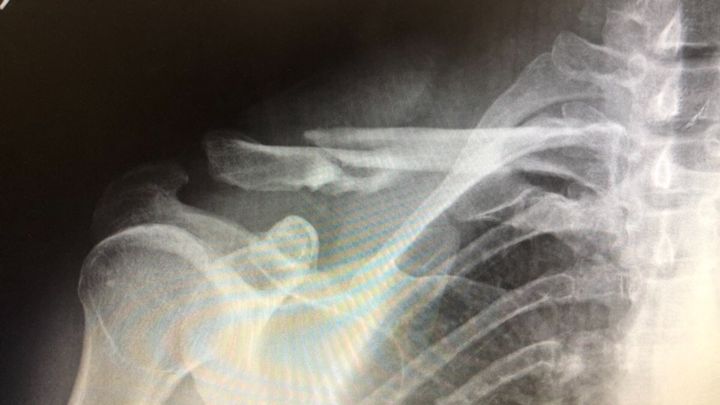

I recently crashed while downhill mountain biking in Colorado. It was at a decent rate of downhill speed causing me to flip over my handlebars absorbing impact onto/into my head/neck/shoulder. This caused a comminuted clavicle fracture that is also displaced with bone fragments all over. My arm is not attached to my body via bone at the moment causing additional pain & stress to the ligaments that typically hold that in place. This particular case will require surgery that is semi invasive to get me to a place that I can function almost fully again to continue with my livelihood, lifestyle & career.